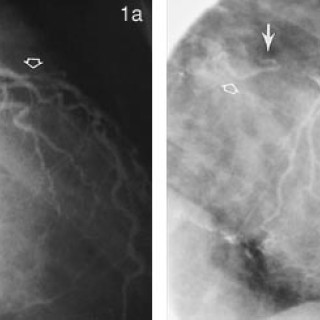

30.08.2000:

Svulster i hjertet forekomme meget sjelden og kun hos 0,002 – 0,03 % av uselekterte pasienter i store obduksjonsmaterialer (1, 2). Ved Sintef Unimed, Norsk pasientregister, ble det i tiårsperioden 1990 – 99 registrert 82 pasienter med godartet svulst i hjertet, mens det i Kreftregisteret i tiårsperioden 1988 – 97 ble registrert ni pasienter med primær, ondartet svulst i hjertet. Karakteristisk ved tumor cordis er at de fleste (80 – 90 %) svulstene er godartede. Tre firedeler av de benigne tumorformene utgjøres av myksomer, mens resten hovedsakelig består av rabdomyomer, papillære...